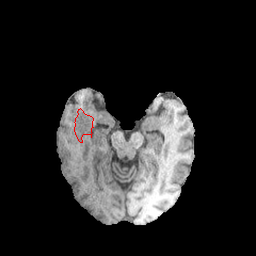

Refer to caption

(a)

(b)

(c)

(d)

(e)

(f)

(g)

(h)

Figure 2: Samples patches from BCSS (a-d) and BraTS 2020 (e-h) with their respective tumor ground truths marked in red.

As the focus of this work is on possible applications of SAM in the medical domains, we evaluate on the radiology dataset BraTS and the pathology dataset BCSS. Figure 2 shows sample patches from both datasets. The following sections provide more details on each dataset.